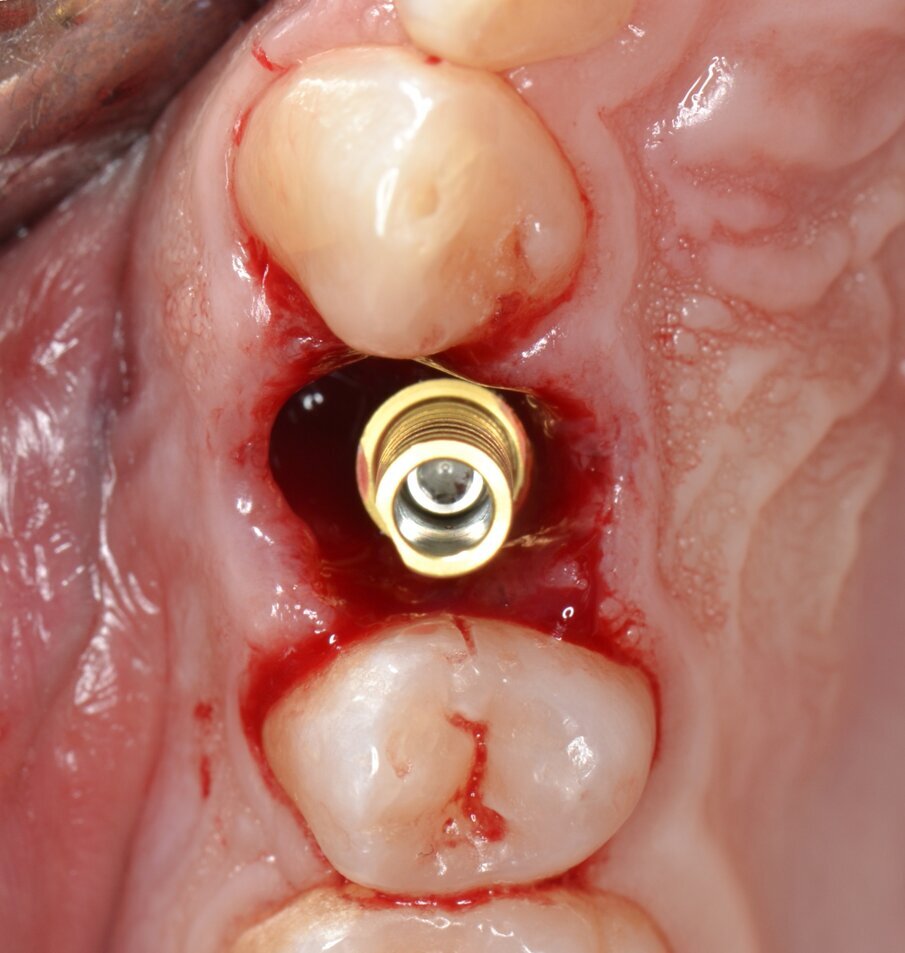

Viene inserito un impianto di tipo “bone level” da 3,5 x 15 mm: il raggiungimento di un torque di inserimento implantare (IT) superiore a 55 N.cm pone l’indicazione ad una procedura di provvisorizzazione immediata, motivo per cui un temporary abutment con una connessione protesica di tipo “platform switching” viene avvitato all’impianto con un torque di 35 N.cm (Figg. 10, 11). Per contrastare l’inevitabile contrazione dell’alveolo postestrattivo, il gap peri-implantare viene innestato con un biomateriale di origine eterologa (Figg. 12, 13). L’innesto viene eseguito con un leggero overbuilding in senso verticale allo scopo di sostenere il margine gengivale (Fig. 14).

Fig. 10 - Impianto inserito in posizione protesicamente corretta (IT > 55N.cm).

Fig. 11 - Moncone provvisorio serrato a 35 N.cm.